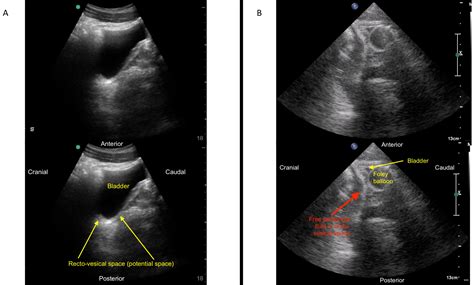

An ultrasound is then conducted to visualize internal organs and structures. The ultrasound technician will apply a gel to the patient's skin and use a transducer to capture images. This step is crucial for examining the heart, abdomen, and other areas of concern.

• fast examination ultrasound

• fast exam ultrasound trauma